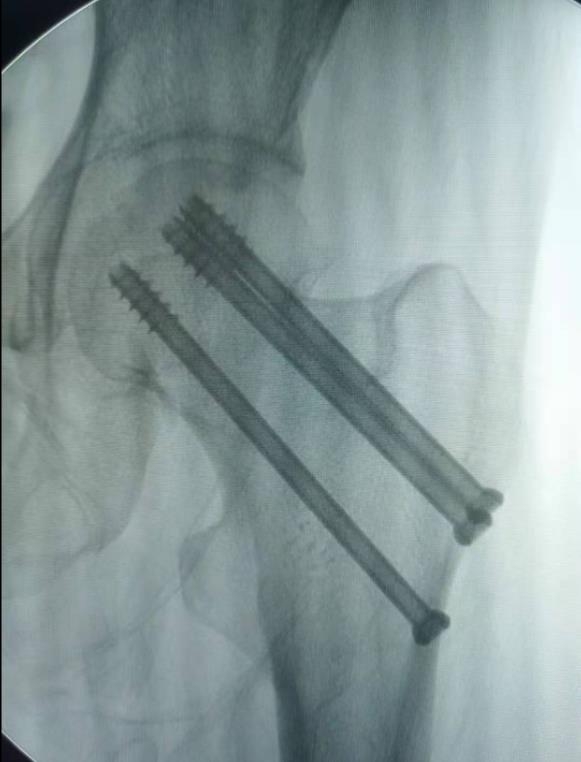

闭合复位经皮固定手术步骤

1、经皮沿股骨颈轴线置入空心钉导针,确保导针平行;

2、标准放置螺钉为倒三角形,其中下方螺钉在股骨矩,后方螺钉在后方骨皮质、研究发现倒三角形平行三枚螺钉能提供最佳的固定强度;

3、螺钉位于股骨颈四周,特别是后侧及下方,避免低于小转子方向进针,可能导致术后转子下骨折;

4、两个平面透视导针位置良好后切开皮肤,空心钻铭孔,导针引导下拧入空心钉,空心钉确保所有螺纹位于骨折线近端,螺钉头应距离软骨下骨5mm。

空心钉固定的三原则:“贴边、平行、倒品”

1、贴边是指3枚螺钉在股骨颈内,尽量靠近外围皮质。这样3枚螺钉作为一个整体,对整个骨折面可形成面状加压,如果3枚螺钉不够离散,更趋于点状加压,稳定性较差,不能较好地对抗扭转和剪切。

有研究显示,在侧位片上,螺钉的前后分布越分散,骨折不愈合发生率越低。J Bone Joint Surg Br. 2005 May: 87(5): 632-4.

3、平行生物力学更稳定。